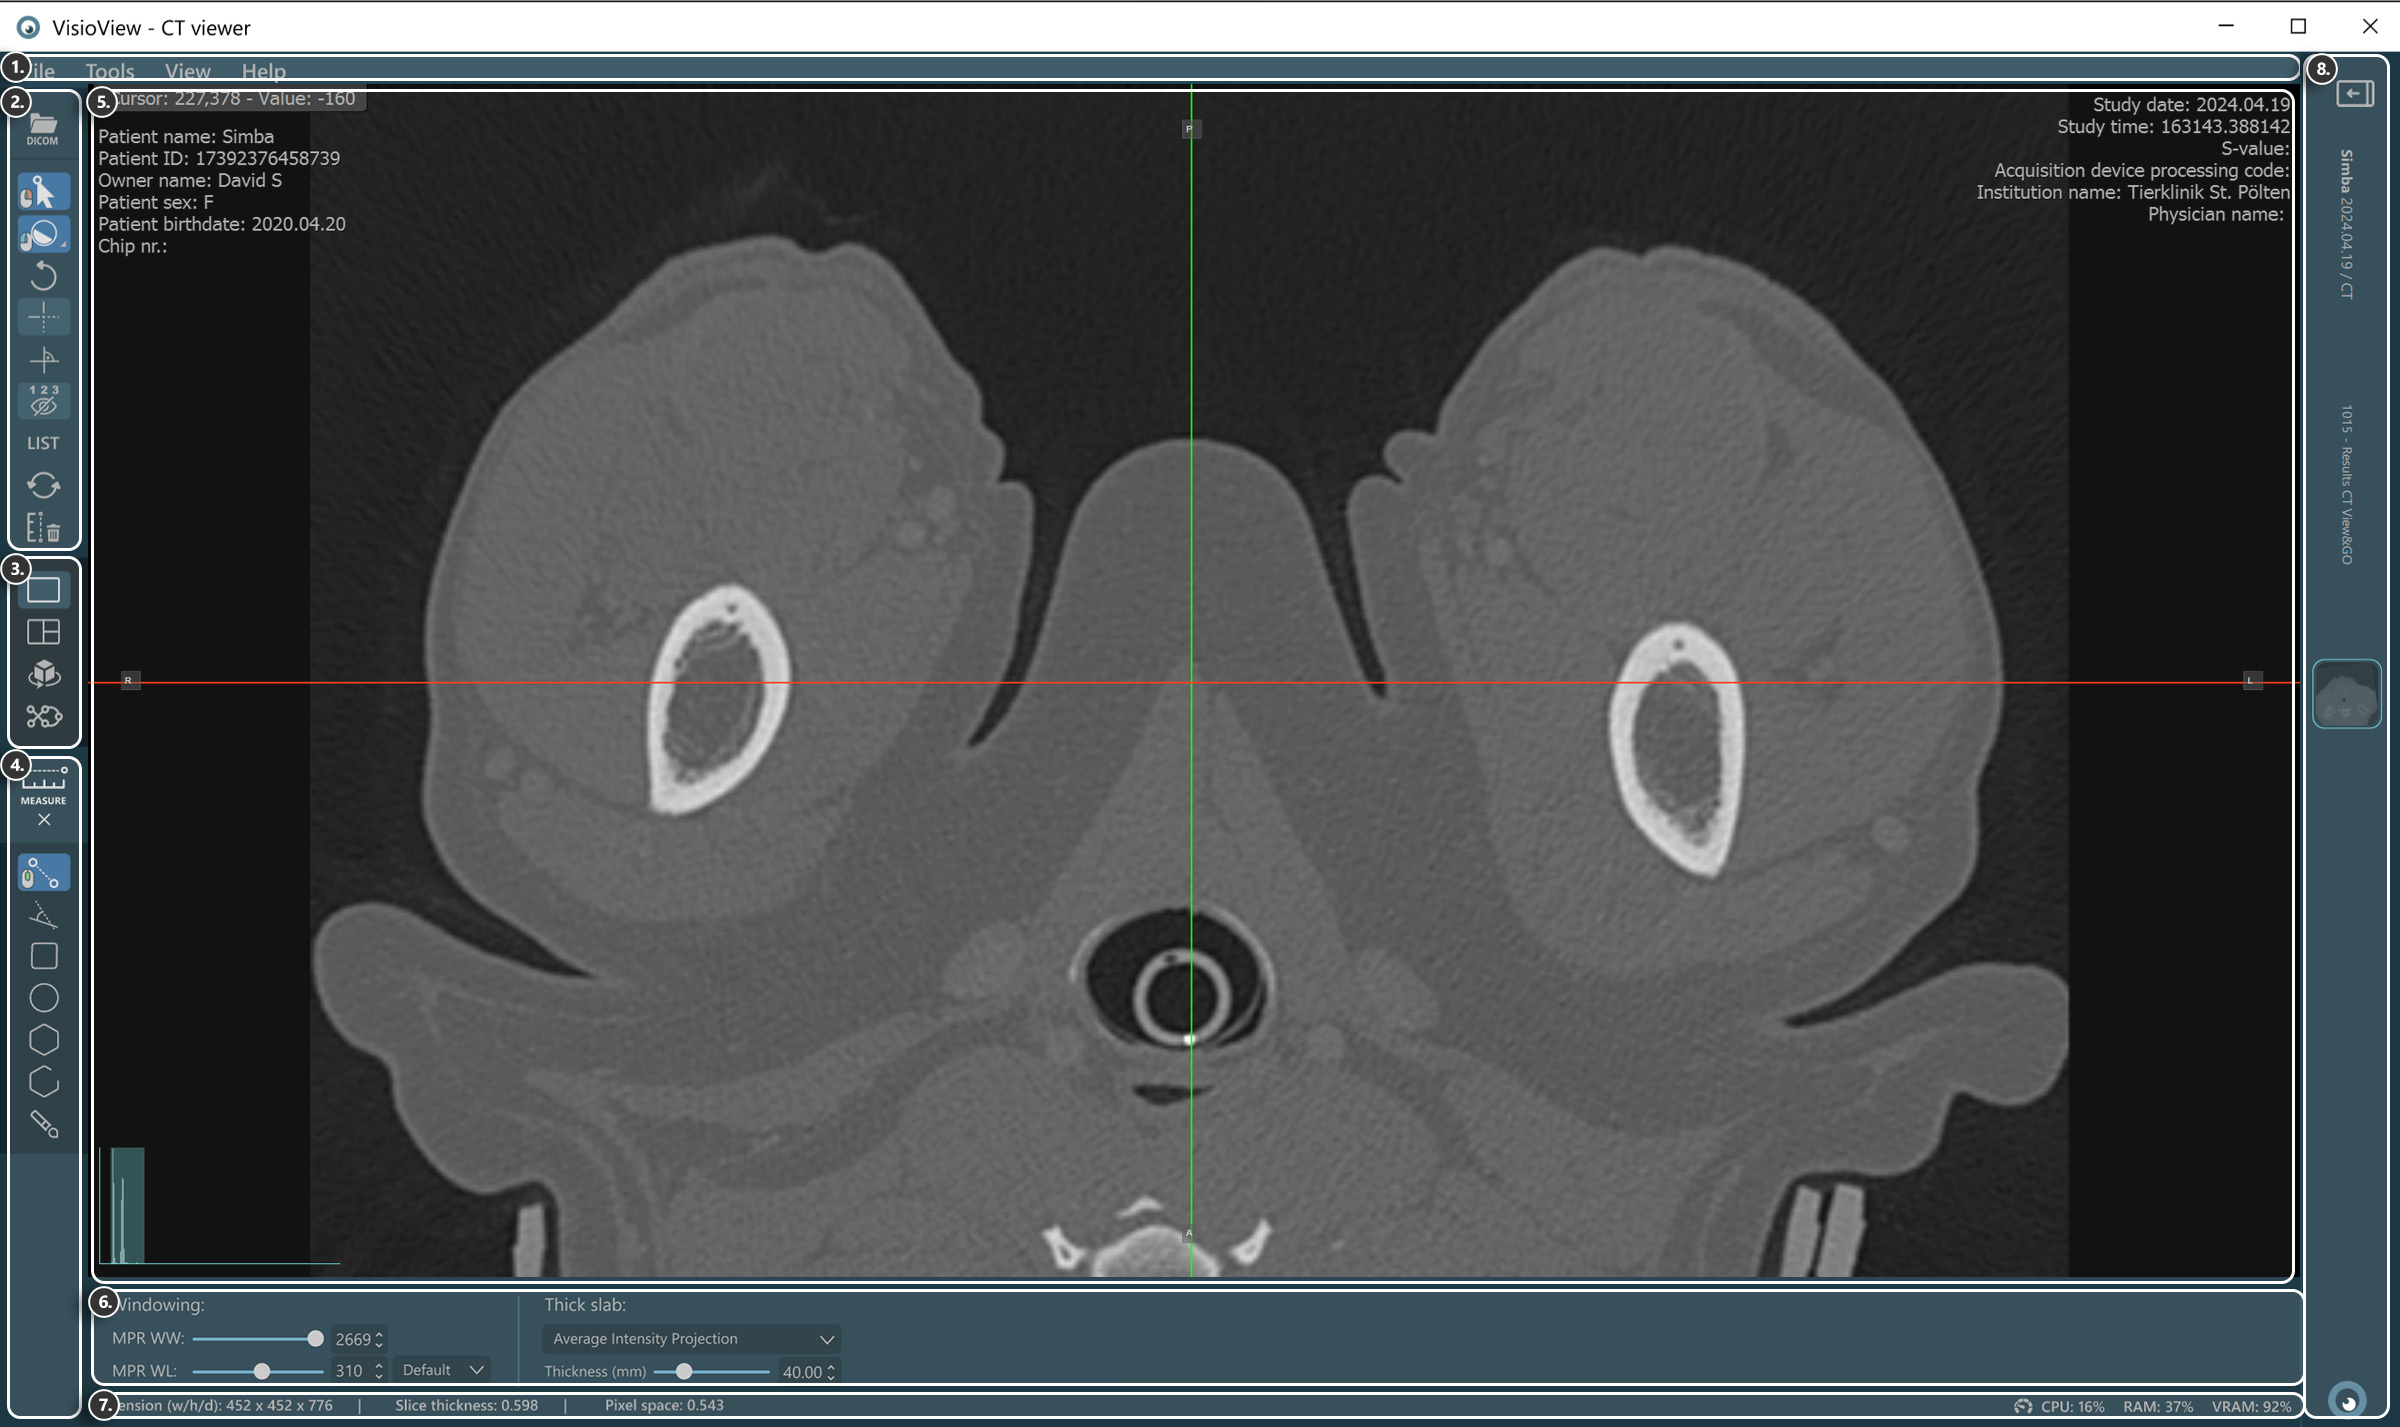

VisioVIEW - CT Viewer¶

The new VisioVIEW CT Viewer is a dedicated DICOM Viewer capable of 3D Multiplanar Reconstruction (MPR) of volumetric DICOM images (CT and MR modalities). Additionally, it also supports other viewing modes, including a 3D view offering simultaneous examination of all 3D planes (Axial, Coronal, and Sagittal) and 3D visualization of the body, a Curved MPR view (CMPR), Average Intensity Projection, Maximum Intensity Projection (MIP), and Minimum Intensity Projection (MinIP).

Sections of the VisioVIEW CT Viewer¶

The VisioVIEW CT Viewer consists of several sections, each tailored to a specific purpose. Below is a detailed description of each section.

Viewer Area¶

HU (Hounsfield Unit) pixel value

Patient information

Windowing histogram tool

Slicers

Study information

View Settings and Options¶

Windowing settings

Thick slab settings

Information Bar¶

DICOM image and resolution information

Performance and resource usage information